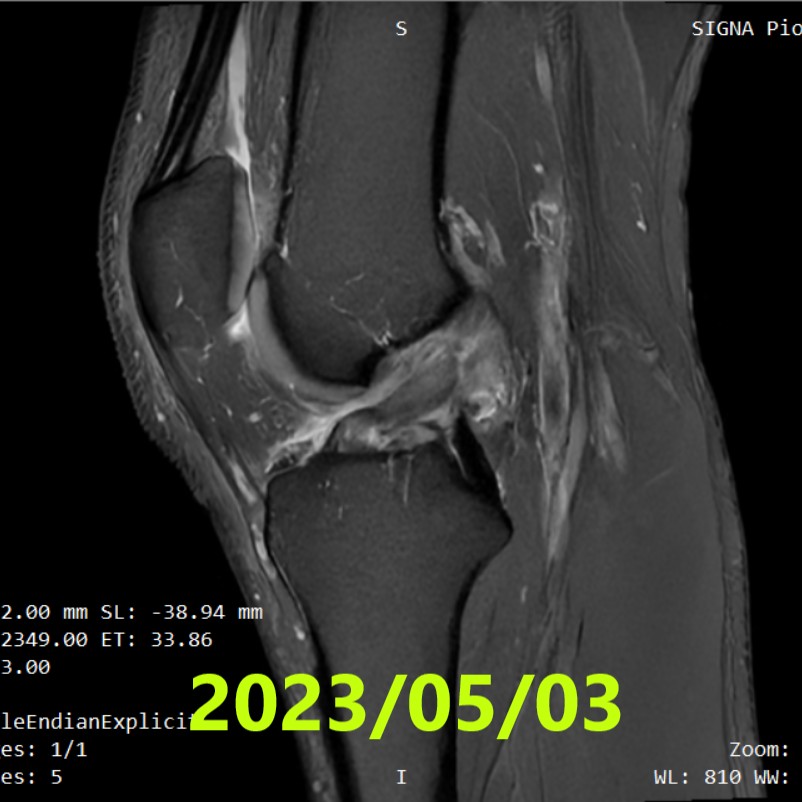

初期評估(MRI ①)

- 拍攝日期:2023年5月3日

- 臨床所見:Lachman 測試陽性,無膝蓋不穩感(Giving-way)

- 影像診斷:委託 3 名獨立的影像診斷專家進行評估

- Ihara分類:3名專家一致判定為 Ⅲ 型(Type 3)(完全斷裂)

- 備註:初期在醫院接受一般的物理治療,包含膝關節完全伸展訓練。

〖Ihara 分類注釋〗

I = 線性斷裂 / II = 弧形斷裂(單純完全斷裂) / III = 伴隨斷端位移的斷裂 / IV = 斷端模糊、形態不良(最複雜)